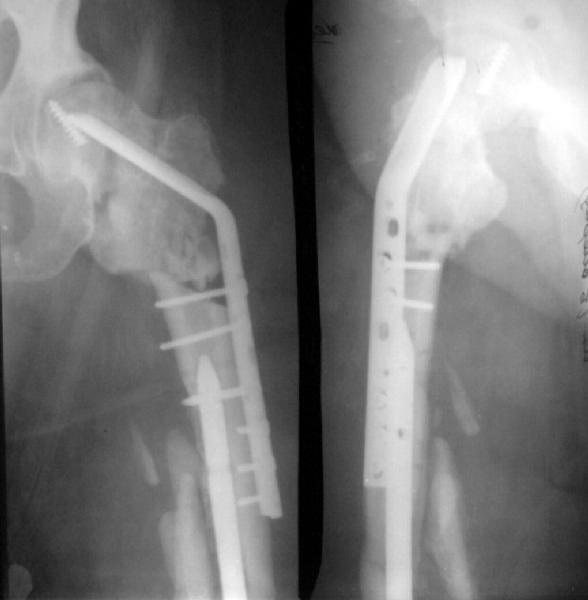

1 year ago a female 44 y.o. was operated on the femoral shaft and neck fractures 2 weeks after a car accident. Closed interlocked nailing was performed, and the neck was fixed miss a nail with poor result mostly due to her obesity - femoral circumference is >80 cm (image 1).

This is a good example of sub optimal placement of the neck screws. Young patients with neck/shaft combo fxs have a high Pauwel's angle. This is counteracted by open reduction and internal fixation in order to reduce caudal portion of fem neck. the screws are angled differently by placing them perpendicular to the fem neck fx line (typical AO technique) or horizontal to the floor. The screws here are similar to elderly fem neck fx types. Therefore, no biomechanical advantage exists and the nonunion is produced.

One potential problem with recommending treatment options for the femoral neck nonunion is that we have no idea what the femoral neck alignment looks like on the lateral view.